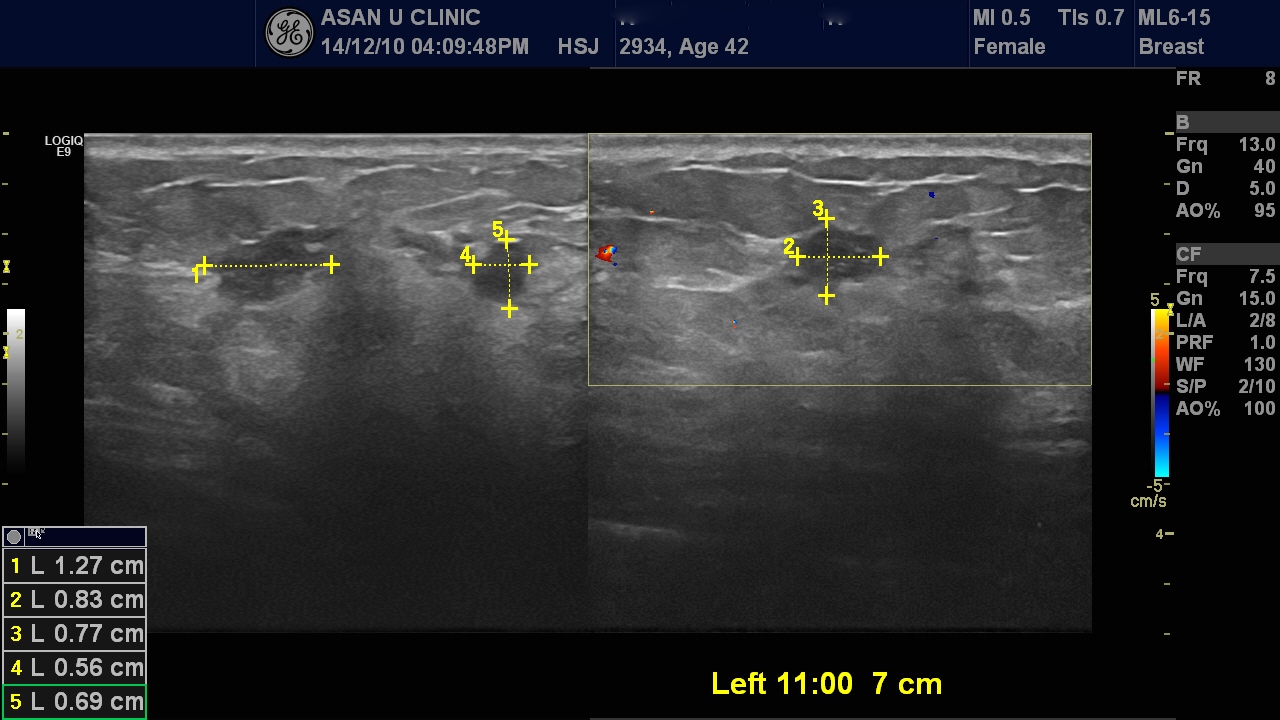

건강검진상 이상소견있어 내원한 42세 여성분입니다.

검진시 실시한 유방촬영상에는 왼쭉유방의 상내측에 불규칙하게 퍼져있는

미세석회화와 음영들이 산재해 있었습니다.

초음파를 실시하였고 악성으로 예상되는 두군데를 조직검사 하였으며

두군데 모두 안타깝게도

침윤성 유관암으로 진단되었습니다.

본원 초음파상엔 겨드랑이 림프절은 커져있는 듯했으나,

여러군데 모래알 처럼 흩어져 있으나

실제 덩어리를 이루는 혹은 작을 수도 있습니다.